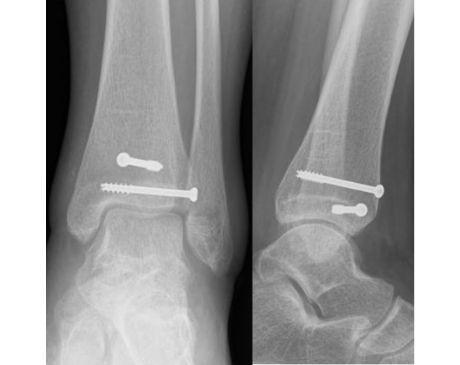

I was hit by car, had a compound fracture with a bone sticking out of my left foot. Broken tibia and fibia?. Screwed plate and bones back together. I am healing fine, next visit 3/26 to remove stiches. I seem to have total function of foot. Still have 2 more weeks of not using leg, but very hopeful.